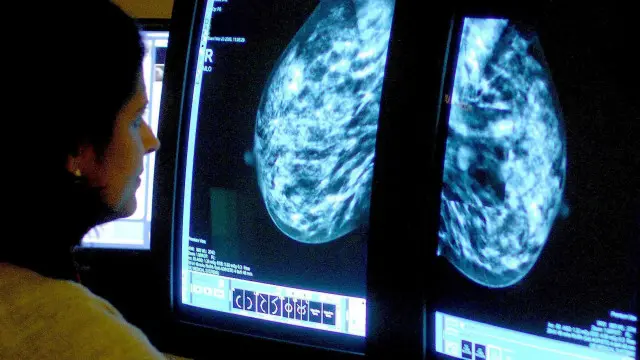

ساينسپوهان وايي يو ارزانه او خوندي درمل کېدی شي له نيمو هغو ښځو سره د ژوند په اوږدوالي کې مرسته وکړي، چې د تيونو په سرطان اخته دي.

دغه څېړنه چې په <link type="page"><caption> نېچر جورنال</caption><url href="http://www.nature.com/nature/journal/vaop/ncurrent/full/nature14583.html" platform="highweb"/></link> کې خپره شوې، په لومړيو پړاوونو کې ده، خو ښيي چې د پروجېسټېرون په نامه د ميندوارۍ هورمون کېدی شي د ځينو ټيومورونو د ودې ورووالي کې وکارول شي.

هورمونونه د تيونو سرطان کې لوی رول لري.

دوی د سرطان پر مخ له "هرمون نيوونکو" سره په نښلېدو سرطاني حجره يا سلول وېشلی شي.

د تيونو سرطان يو تر ټولو بريالی درمل، ټاموکسيفېن، د اويسټروجن هرمون نيوونکي مخه ډب کوي.

د پروجېسټېرون هرمون نيوونکو سرطان په لږ مرګوني بڼې پېژندل کېده، خو دا چې ولې، دليل يې روښانه نه و، او د درملنې په توګه نه و سپړل شوی.

دوی ښيي چې د پروجسټېرون نيوونکی او د اويسټروجن نيوونکی دواړه په نژدې ډول سره تړلي دي، او دا چې د پروجېسټېرون نيوونکی د اويسټروجن نيوونکي بدوالی کمولی شي.

سرطاني حجرې يا سلولونه چې په لابراتوار کې يې وده کوله، د يوازې ټاموکسيفېن ورکړې پر ځای يې چې کله په پروجېسټېرون او ټاموکسيفېن درملنه شوې، په نيمه کچه يې وده کړې ده.

شاوخوا ۷۵٪ سلنه ښځې چې د تيونو په سرطان اخته کېږي، په اويسټروجن نيوونکي سره وي، او سلنه ۷۵٪ يې پروجېسټېرون نيوونکي هم لري.

دغه څېړنه ښيي چې نژدې نيمې ښځې ښايي له دې ډول درملنې ګټه واخلي.